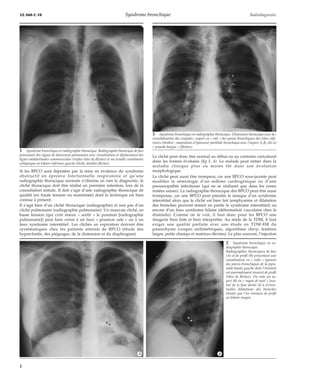

9 Trachée en « lame de sabre ».

A. Sur la radiographique thoracique de face, la question d’une tumeur latérotrachéale

droite peut être envisagée (flèche).

B. Le profil semble rassurant.

C. La tomodensitométrie confirme en montrant l’absence de tumeur et de déformation

trachéale dans le plan antéropostérieur avec rotation à droite expliquant l’aspect pseu-dotumoral

en projection de face (flèches).

10 Classification de Reid

et visualisation tomodensi-tométrique

(TDM) des dila-tations

des bronches. De-puis

1987, l’aspect TDM

des bronchectasies est bien

connu.

A. Bronche normale

et son vaisseau.

B. Bronchectasie cy-lindrique

en « bague

à chaton ».

C. Bronchectasie mo-niliforme.

D. Bronchectasie kys-tique.